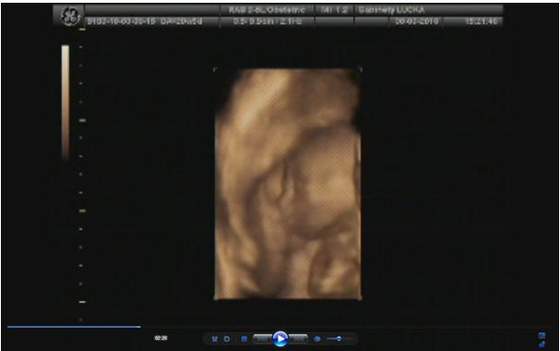

a lekarz na to "bardzo serdecznie zapraszam"

no niby 3500 ale to raczej mało możliwe (sam przyznał) skoro 2 tygodnie temu miała 2700

ale usg było jakie było i kazał się tym nie sugerować -ważne że urosła